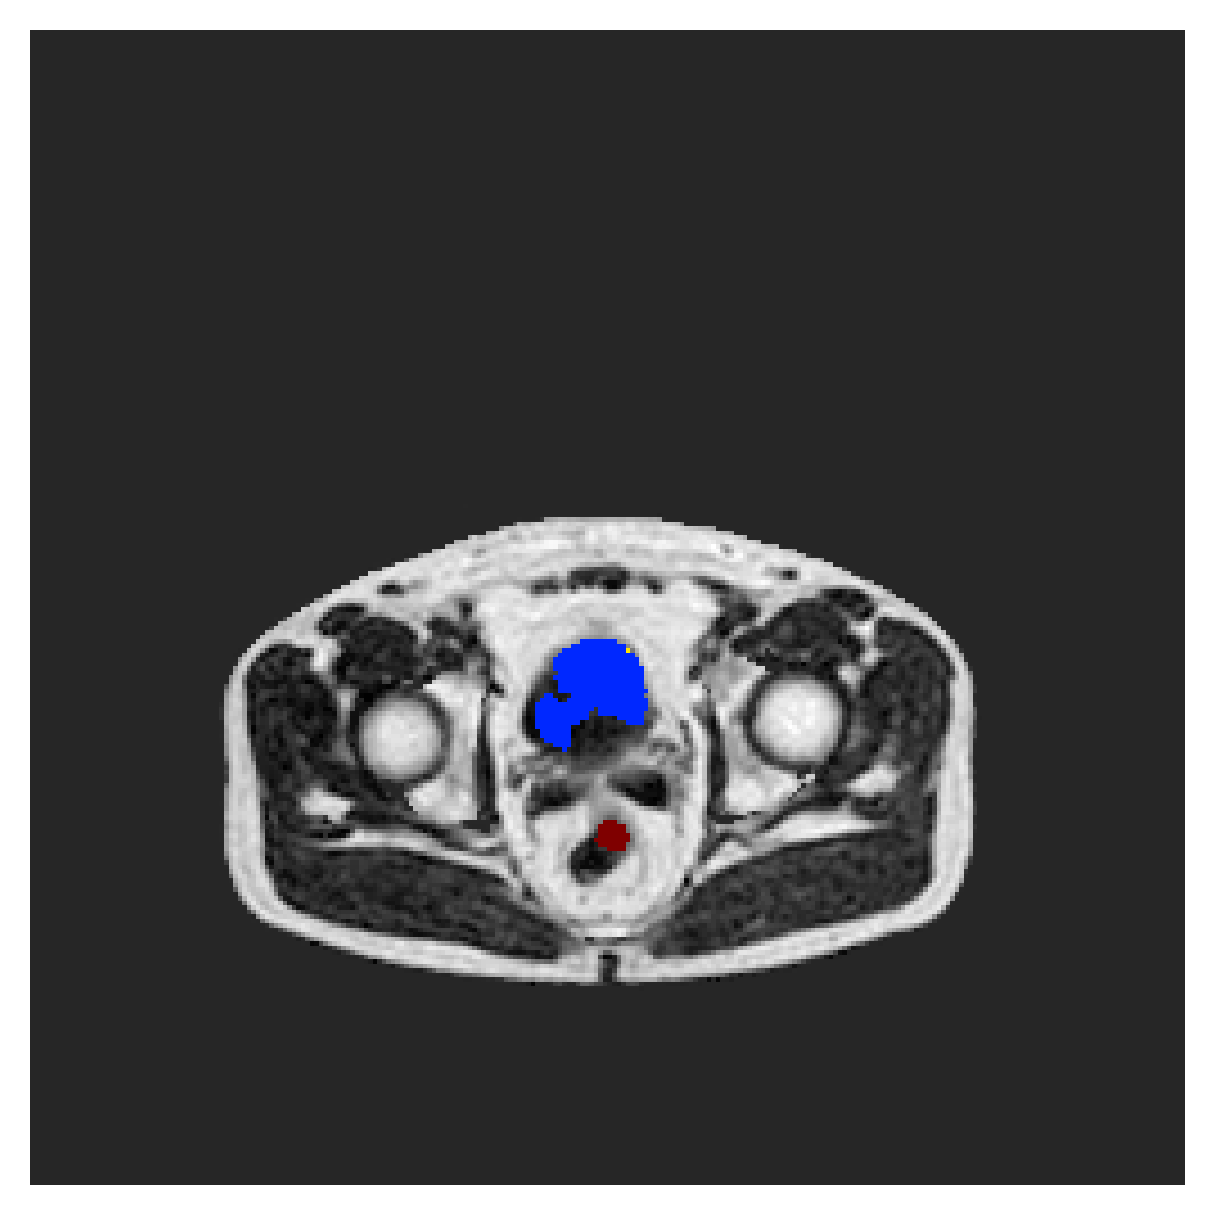

We normalize the volumes and resize the slices to pixels. As the official dataset comes with full annotations, we create a synthetic point ground truth. This is done by first randomly choosing the centers of the point annotations within the class masks, followed by filling an ellipse with axes lengths of and (in pixels) around each center. The intersections of these elliptic discs with the underlying full annotations are then used as our point ground truth. See Figure 2 for an example of the created weak annotation mask. The point annotations are created for every slice, one for each foreground object present in the slice.

Qualitative comparison

|

|

|||

|

|

|

|

|

|

|

|

|

|

|

|

| (a) Ground truth | (b) , full | (c) , weak | (d) |

| (full) | supervision | supervision | |

|

|

|

|

|

|

|

|

|

|

|

|

| (e) | (f) | (g) | (h) CRF-loss |

In Figure 6 we provide qualitative results on a number of randomly chosen test set slices. Upon visual inspection, we can observe that training with the intensity-aware distances (particularly with and ) follows the image gradients better and is better at recovering the underlying shape than the Euclidean version. The CRF-loss seems to recover the shape of the myocardium and left ventricle to some extent, but fails entirely on the right ventricle.